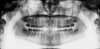

Extraoral Digital Radiography

As with intraoral digital radiography, extraoral digital images can be acquired using direct or indirect digital imaging systems. Digital panoramic and cephalometric machines are available that utilizes either linear array CCD or CMOS detectors or PSP plate sensors. With CCD or CMOS extraoral imaging, conventional film is replaced by a long, vertical, rigid digital receptor a few pixels wide.31 With PSP receptors, the plate is configured in the same dimensions as panoramic or cephalometric film and can be placed directly into the cassette with the intensifying screens removed. As with intraoral direct digital imaging, a patient file must be created, the appropriate template or projection selected, patient positioned, exposure made, and image viewed on the monitor (Figure 5). With PSP plate receptors, the plate needs to be scanned before the image can be viewed. The technique for preparing and positioning the patient is similar to conventional panoramic and cephalometric radiography. In addition, errors can be produced when the patient is improperly prepared and the head alignment does not conform to technique requirements. The quality of the resulting image is ultimately the responsibility of the clinician and proper application of extraoral imaging techniques.

Both film-based and digital formats produce comparable images with spatial resolution of 3 lp/mm to 4 lp/mm for PSP receptors and 6 lp/mm to 8 lp/mm for CCD receptors.32 As with intraoral digital imaging, elimination of the darkroom, the ability to enhance9 and analyze the image,33 and the convenience of image storage, duplication, and retrieval are beneficial. With extraoral imaging, the file size is considerably larger than intraoral imaging and must be reduced by compression techniques that facilitate stor­age but do not compromise the diagnostic quality of the image.

Figure 5. A digital extraoral radiographic image is displayed on the computer monitor. This particular radiographic projection is a lateral head plate. (Patterson Dental Supply, Inc)

Figure 5